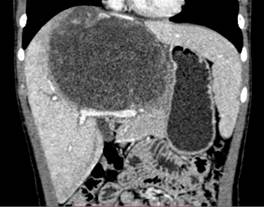

图10:示肝中叶肝脏肉瘤CT所见

CT提示巨块肿瘤可侵占一或两叶肝。肿瘤呈椭圆形或大分叶状低密度肿块。CT所见取决于大体病理。可为分隔多房的囊性肿物,囊腔大小不一呈水样密度,粗细不匀的分隔为肿瘤的实性部分,密度与肌肉相仿,CT值约35HU。周围有假性包膜。有时肿瘤呈单一大囊腔,内含无定形絮团状阴影,部分呈蜗轮状,内壁见高密度息肉阴影附着示肿瘤内出血。肿瘤亦可以实性为主,内含多数小囊。肿瘤血供多少不定,囊性病变明显的病例,血供一般较少或无血供。增强扫描,实性部分及包膜可有强化,囊性部分增强不明显,CT值在22~28HU,偶见钙化。本病需结合临床、影像学所见与间叶错构瘤鉴别。

为儿童期少见肿瘤,占小儿原发性肝肿瘤的第四位。发病年龄大多6~10岁,亦可见于成人及幼童。临床主要表现为上腹部肿物,伴有发烧、黄疸和体重下降。肿瘤发生于肝内,右叶比左叶多见。该肿瘤生长迅速,恶性度高,晚期转移至肺及骨骼,存活期多为一年左右,预后不良。